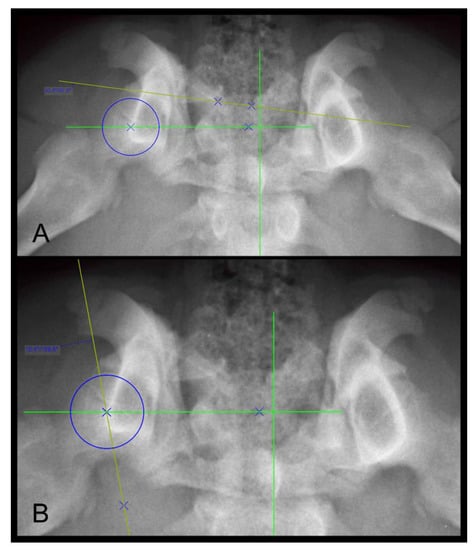

2.5.6. Dorsal Acetabular Rim Slope (DARS)

The DARS is the angle between the intersection of the perpendicular line drawn from the center of the femoral head to the mid-sagittal plane of the pelvis/sacrum, and the line drawn tangent to the most lateral point of the dorsal acetabular rim [33]. The DARS is reported to be ≤7.5° in healthy hips, whereas higher values indicate hips with increased laxity [33]. The measurement of the DARS on a DAR-view radiograph is shown in Figure 3A.

2.5.7. The Center Edge Angle (CEA)

The CEA is an angle between the straight line, drawn from the center of the femoral head tangential to the outer edge of the acetabular rim, and the straight line, drawn parallel to the mid-sagittal axis of the pelvis/sacrum on DAR-view radiographs [35,36]. The CEA is used to assess the acetabular coverage of the head of the femur and is reported to be greater than 12° for healthy hips [36]. The magnification of the measurement of the CEA in a Rottweiler dog is shown in Figure 3B.

Figure 3. Dorsal acetabular rim view radiographs of the same Rottweiler shown in Figure 1 A,B as well as Figure 2. Measurement of the dorsal acetabular rim slope is demonstrated on (A) and of the center edge angle on (B). Right is always to the left of the image.